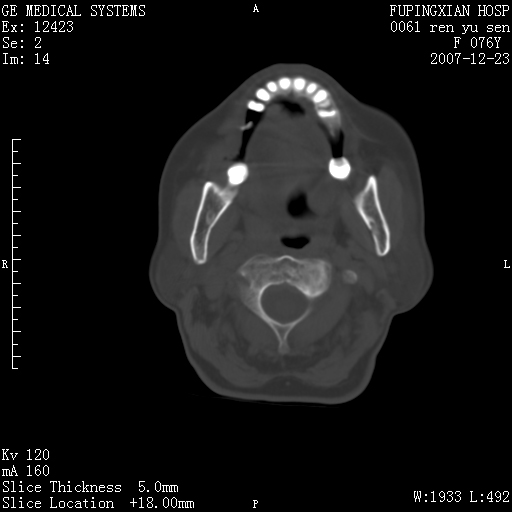

男性 76岁 下颌右侧磨牙区肿物数月, 约2.0*1.5cm大小波及颊舌侧,伴颌下淋巴结肿大。余(-)

右颈部颌下腺前可见一类圆形软组织密度影,密度不均,内见小片坏死区.颌下颈前可见两枚肿大淋巴结影.考虑淋巴结感染可能性大,建议增强扫描..

考虑牙周炎并颌下淋巴结肿大(感染)可能!

右侧第四磨牙缺失,局部牙槽骨质破坏,边界欠清晰,同侧颌下及竟不见多发肿大淋巴结显示。考虑肿瘤病变可能性大,感染待排